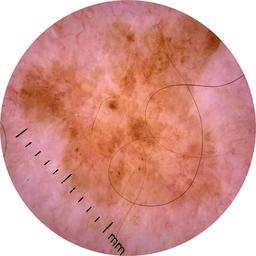

ISIC_6813604

MEL-SELF Trial, https://www.sydney.edu.au/medicine-health/our-research/research-centres/melself-project.html

acquisition_day 624

age_approx 75

anatom_site_1 Head and neck

anatom_site_general head/neck

diagnosis_1 Benign

diagnosis_confirm_type single image expert consensus

fitzpatrick_skin_type I

image_type dermoscopic